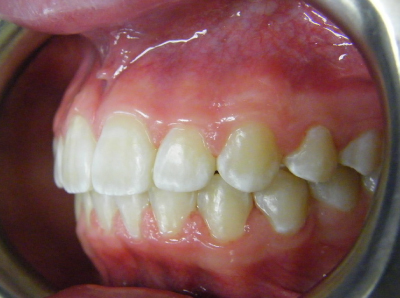

The first two sets of photos below are the before and after photos of a patient who had expansion of the upper jaw followed by upper and lower fixed braces. The third set of photos shows a patient with an expansion plate bonded to the upper teeth and lower fixed braces.